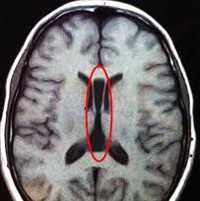

Интересно, что в этой же группе достоверно чаще отмечались случаи трифуркации внутренних сонных артерий (Рис. 1).

Рисунок 1. Больная Б., 20 лет. Задняя трифуркация правой ВСА. МР ангиограмма.

Учитывая, что указанная патология изменяет территорию васкуляризации мозговой ткани и существенно снижает возможность развития сосудистых коллатералей и обеспечение мозга кислородом [8], она может рассматриваться как патогенетический фактор, утяжеляющий течение болезни, и гипотетически как один из факторов риска ее развития.